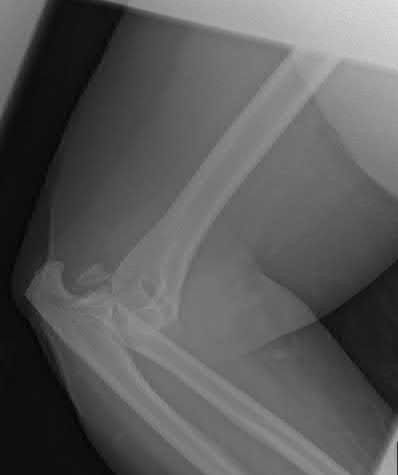

An 85-year-old female with severe rheumatoid arthritis and osteoporosis sustains a highly comminuted, intra-articular distal humerus fracture (AO/OTA 13-C3) after a mechanical fall. She lives independently and uses a walker. Which surgical intervention provides the most predictable pain relief and allows for immediate postoperative weight-bearing through the upper extremity for mobility?

Explanation

In an elderly, osteoporotic patient (especially with a history of inflammatory arthritis like RA) who sustains a highly comminuted intra-articular distal humerus fracture, Total Elbow Arthroplasty (TEA) provides superior outcomes compared to ORIF. It offers more predictable pain relief, earlier return of function, and allows the patient to bear weight immediately (within standard TEA limits, though essential for immediate walker use) without the high risk of hardware failure or nonunion associated with osteoporotic bone.